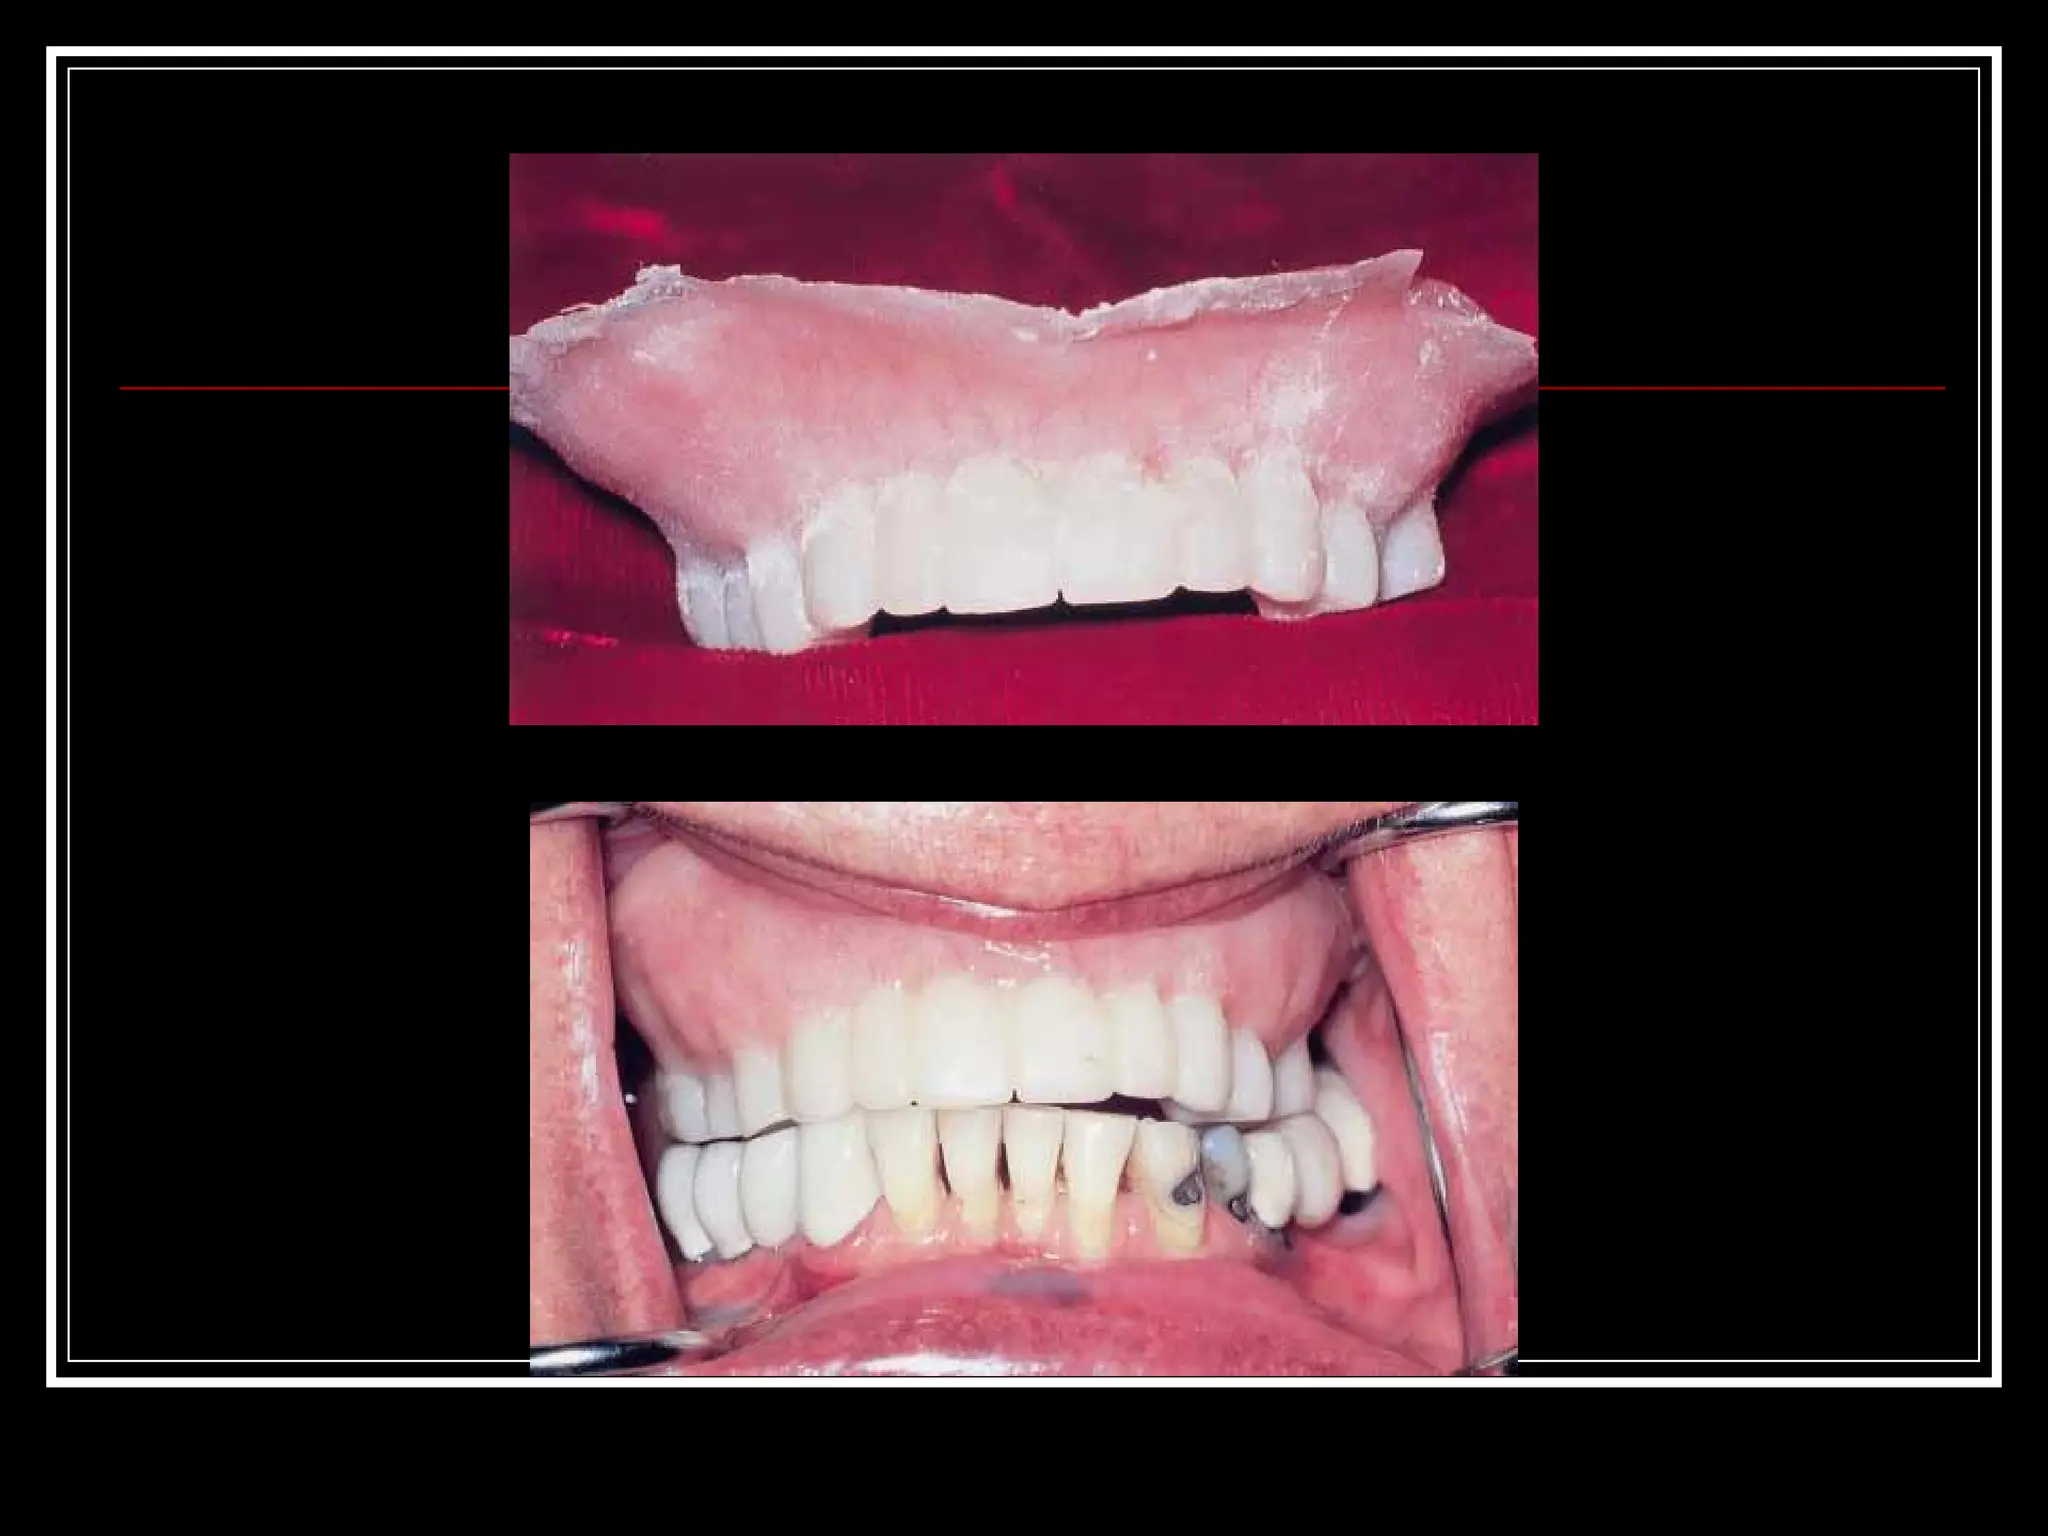

Ashok Soni etal (2000)  Trial anterior artificial tooth arrangement for an immediate denture patient :A clinical report  A technique is described that allows the esthetic try-in of the maxillary anterior artificial tooth before the extraction and completion of an immediate denture

Intra oral view Posterior artificial tooth try in done with modified anterior wax up in anterior labial flange area.

Try in ofposterior artificial tooth arrangement with processed maxillary denture.

 To relatethe maxillary denture to remaining teeth and supporting tissues, an impression of the adjusted denture was made and a new maxillary cast fabricated.

 The maxillary artificialanterior teeth were arranged to reflect the position of the patients natural teeth.

 Labial indexof the completed anterior artificial tooth arrangement was made with impression plaster.

 After theseparation of the index the teeth were fixed using autopolymerizing acrylic resin.  Denture was finished and inserted immediately after the extraction.